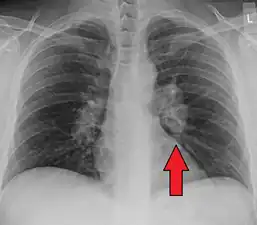

![]() | |

| Chest X-ray showing the typical nodularity of sarcoidosis, predominantly in the hila of the lungs. | |